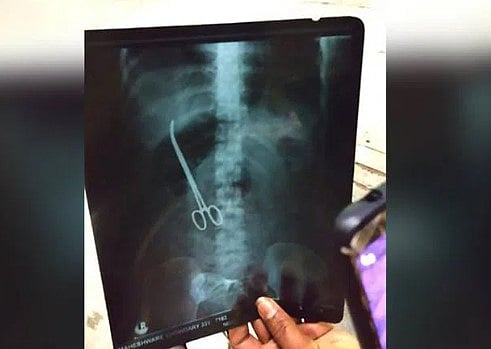

இதனால் அவர் விஜயவாடா மருத்துவமனைக்கு சென்றுள்ளார். அப்போது அவருக்கு எக்ஸ்ரே எடுத்துப் பார்த்தபோது வயிற்றில் கத்தரிக்கோல் இருந்தது தெரியவந்தது. இது எப்படி வயிற்றுக்குள் சென்றது என விசாரித்தபோது, பிரசவத்தின் போது மருத்துவர்கள் தவறுதலாகக் கத்தரிக்கோலை வைத்துத் தைத்தது தெரியவந்தது. பின்னர் அறுவை சிகிச்சை செய்து அவரது வயிற்றிலிருந்து கத்தரிக்கோலை மருத்துவர்கள் அகற்றினர். தற்போ இந்த சம்பவம் வெளியே தெரிந்து பரபரப்பை ஏற்படுத்தியுள்ளது.